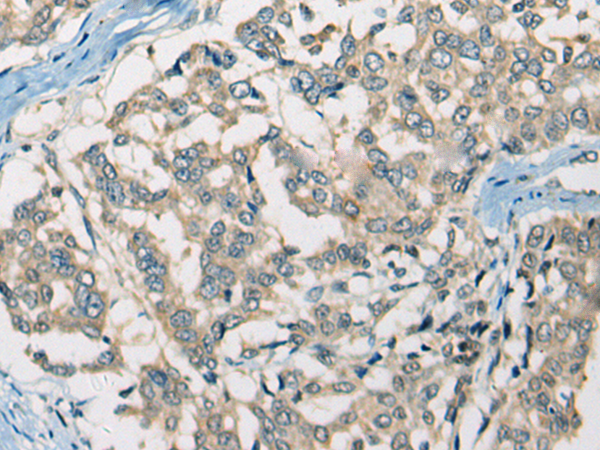

分类: 科研抗体货号: P12172别名: CD33L3; HsT1361; SIGLEC-15应用: IHC反应种属: Human